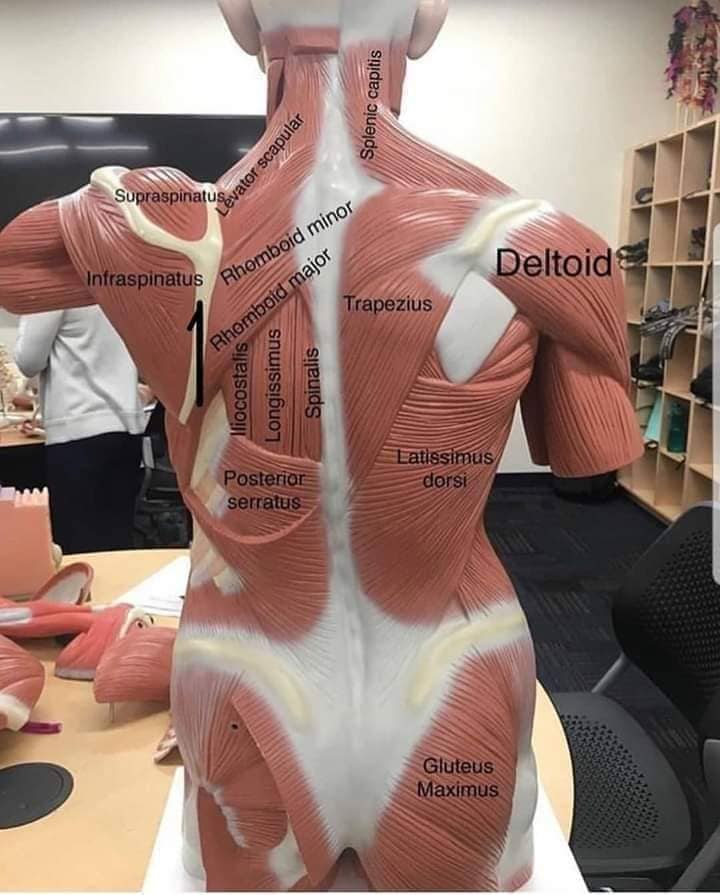

Спинні м'язи

Спинні м'язи виконують функції підтримки хребта, а також дозволяють здійснювати рухи тулуба.

Поверхневі спинні м'язи

М'язи, що піднімають лопатку: Трапецієподібний м'яз: великий м'яз, що покриває верхню частину спини. Його функція - підтримка і рух лопаток, а також забезпечення стабільності хребта.

М'язи, що ведуть лопатку до хребта: Широкий м'яз спини: великий м'яз, що розташований в нижній частині спини. Він відповідає за рухи плечей і лопаток, а також за розширення верхньої частини тулуба.

Глибинні спинні м'язи

М'язи, що забезпечують стабільність хребта: М'язи, що розташовані між хребцями: включають мускулатуру, яка забезпечує стабільність і підтримку хребта, а також дозволяє здійснювати рухи хребта.

М'язи, що здійснюють ротацію та нахили

М'язи, що забезпечують ротацію хребта: Ротаційні м'язи: допомагають у здійсненні обертальних рухів тулуба, а також у підтримці рівноваги і стабільності хребта.